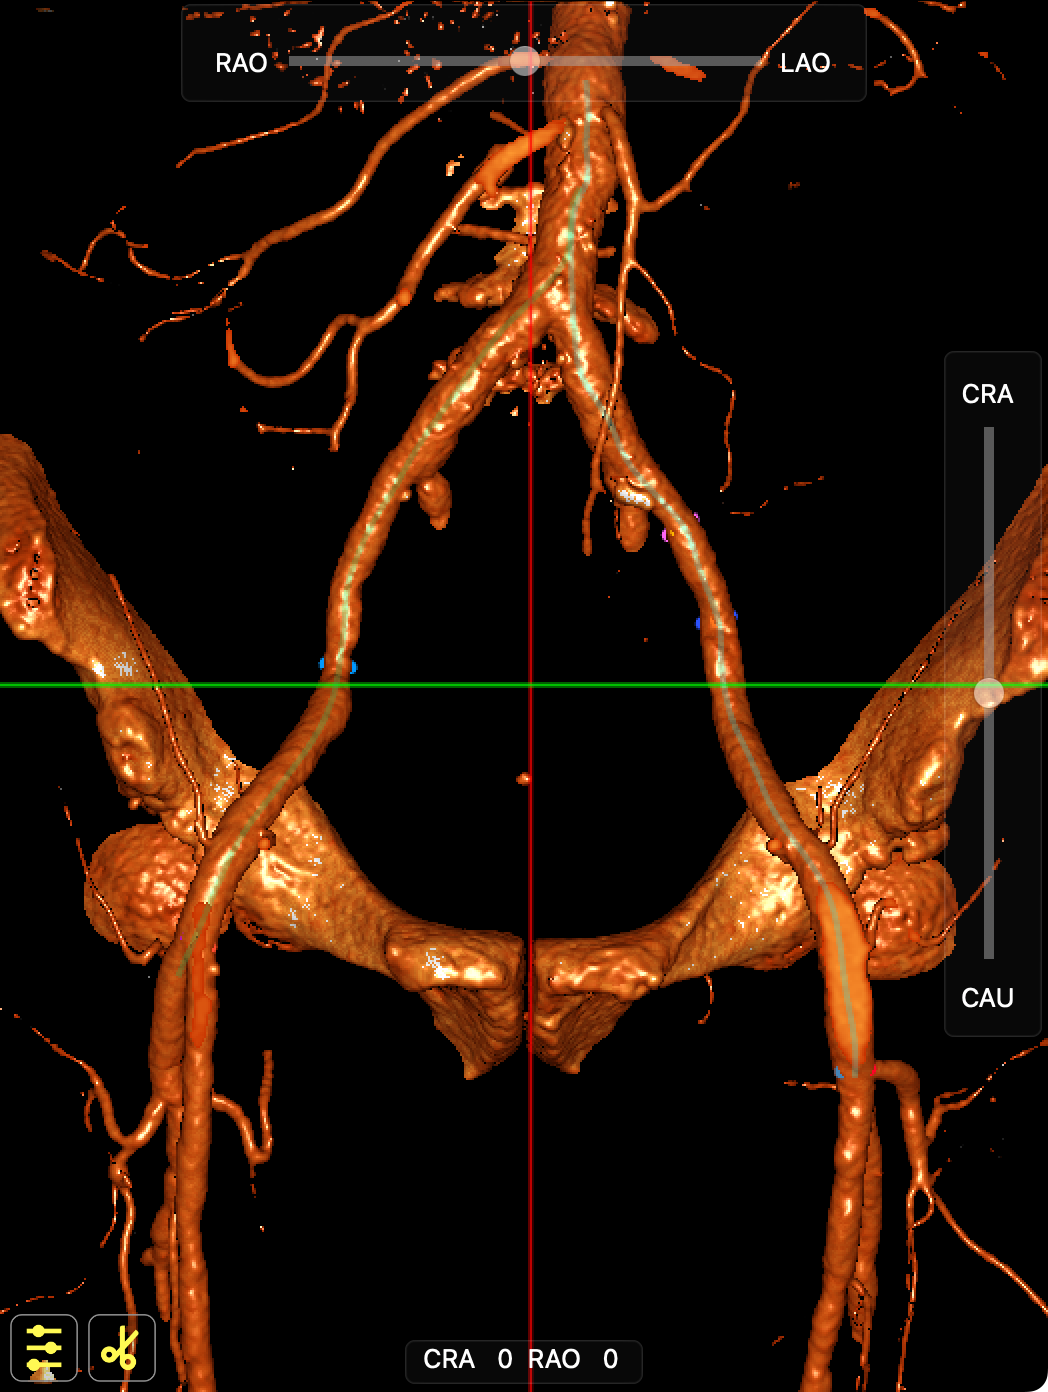

CT影像

CT影像